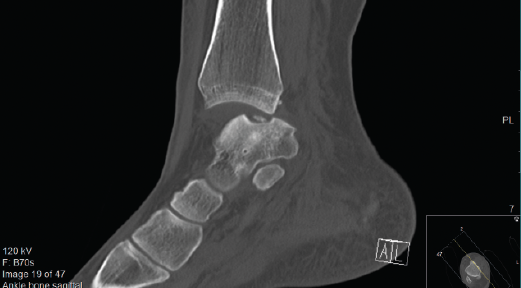

Otras clasificaciones están basadas en la tomografía axial computarizada (TAC) o en la resonancia magnética (RM) y engloban las LOC tanto agudas como crónicas. El estudio mediante TAC permite más precisión para definir el tamaño y la localización de las lesiones, así como de la presencia de cambios quísticos. Ferkel y Sgaglione desarrollaron un sistema de clasificación basado en la TAC (Figura 2), que tiene la particularidad de servir de apoyo para la planificación preoperatoria y la elección del tipo de tratamiento más adecuado (tornillo/pin, microfractura o injerto)(18).

Figura 3. Imagen de tomografía axial computarizada de un estadio III que muestra un fragmento no desplazado con lucencia por debajo.

Una TAC helicoidal ayudará preferiblemente en la planificación preoperatoria, ya que permite caracterizar mejor el tamaño de la lesión, su ubicación y el grado de desplazamiento(31). Eso sí, a expensas de una mayor exposición a la radiación.